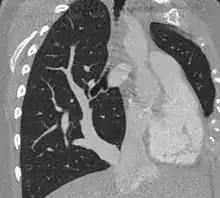

| Scimitar syndrome chest CT | |

The diagnosis is made by transthoracic or transesophageal echocardiography and selective pulmonary angiography.[5] More recently by CT angiography or MR Angiography.